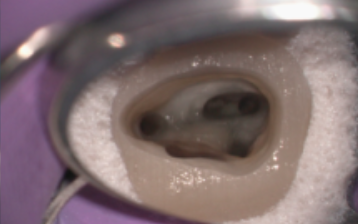

マイクロスコープ

肉眼では確認できない根管内部を

明視野下かつ高倍率で見る

精密根管治療に必要不可欠

「精密」な根管治療

マイクロスコープやCTなど最先端の設備を駆使して、肉眼では見えない根管の微細な構造に至るまで確実に把握。精度を極めた治療で、不必要な削除を避けて、できる限り歯を残します。